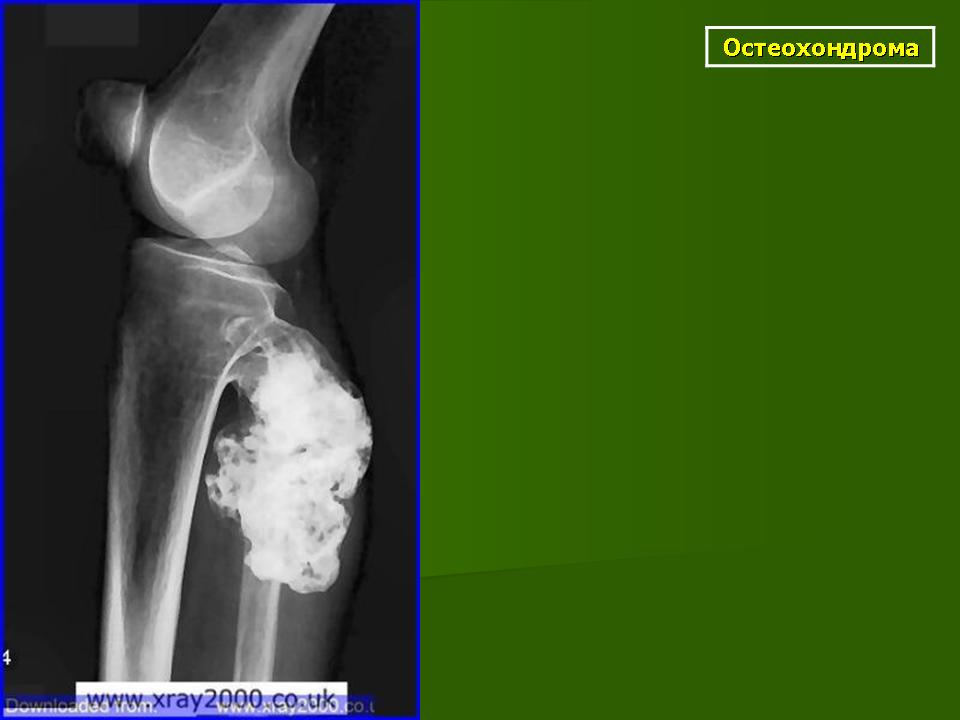

Остеохондрома.

Локализация остеохондромы: частота поражения отдельных костей различна; нижний коней бедренной кости, верхние отделы плечевой и большеберцовой костей поражаются более чем у половины больных. На всем протяжении остеохондрома покрыта надкостницей. Она может быть обнаружена и в других костях, за исключением костей лицевого черепа. Все же поражение костей позвоночника, кистей рук и стоп встречается редко. При рентгенологическом исследовании видна типичная картина узкого или широкого выроста вблизи эпифизарной части пораженной кости. Обычно плотность узла неоднородная, имеются многочисленные плотные участки, соответствующие обызвествленным хрящевым долькам. Хрящевая «шапочка» большей частью не определяется, поскольку хрящ остается необызвествленным. Она может быть выявлена только при магнитно-резонансной томографии.